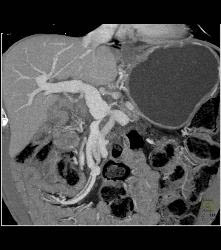

Gastric Lymphoma With Nodes and Ulceration